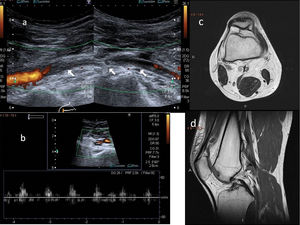

La ecografía Doppler se usa como método de cribado, al ser no invasiva y no emitir radiaciones. El estudio de la AP comienza por encima de la articulación de la rodilla hasta que se bifurca y de manera bilateral. El estudio se realiza con el paciente en decúbito prono, con la pierna extendida y en posición neutral para establecer los cambios de la capa íntima del vaso, la presencia de estenosis o aneurismas, así como la velocidad y la morfología de la curva espectral16,18. La segunda parte del estudio consiste en las maniobras de estrés, en las que el tobillo se coloca en dorsiflexión y flexión plantar hasta 30 segundos, donde el radiólogo puede ayudar a mantener la postura mediante presión (fig. 9 A). Posteriormente, el paciente se pondrá en bipedestación, sobre la punta de los pies15,16. Durante este momento evaluaremos el flujo en todo el recorrido de la AP y evaluaremos la presencia o ausencia del flujo y la disminución del pico sistólico con las maniobras de estrés (fig. 9 B). También podremos evaluar la arteria pedia y la arteria tibial posterior17,19.

Maniobras de estrés para valoración del síndrome de atrapamiento poplíteo. Paciente en decúbito prono, con la pierna extendida y el tobillo en dorsiflexión (A) y extensión plantar (B) durante 30 segundos. El radiólogo puede ayudar a mantener la postura mediante presión. Se evaluará la presencia, ausencia o cambios en el flujo de todo el recorrido de la arteria poplítea con los cambios de posición. C y D muestran hallazgos normales en Doppler espectral con las maniobras de estrés de flexión y extensión.

El flujo turbulento con aliasing es necesario para detectar una estenosis hemodinámicamente significativa. Se considera que hay una obstrucción de los vasos si no se detecta flujo ni por Doppler color ni pulsado18 (fig. 10). Para visualizar las variantes anatómicas correctamente, podremos complementar el estudio con una angio-RM.

A y B) Ecografía Doppler. Suboclusión de la arteria poplítea con flujo muy débil en paciente joven con síndrome de atrapamiento poplíteo y clínica de claudicación intermitente. C y D) Resonancia magnética sin contraste, proyecciones axial y sagital, respectivamente. Inserción anómala del músculo gastrocnemio medial cuyo tendón asciende más de lo habitual, pasando entre la arteria y la vena poplítea, hasta insertarse en la cortical posterior de la metáfisis femoral, donde se ha formado una excrecencia ósea benigna. Clasificación de Love y Whealan II.